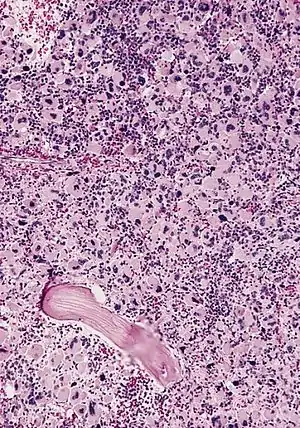

| AML-M7, bone marrow section | |